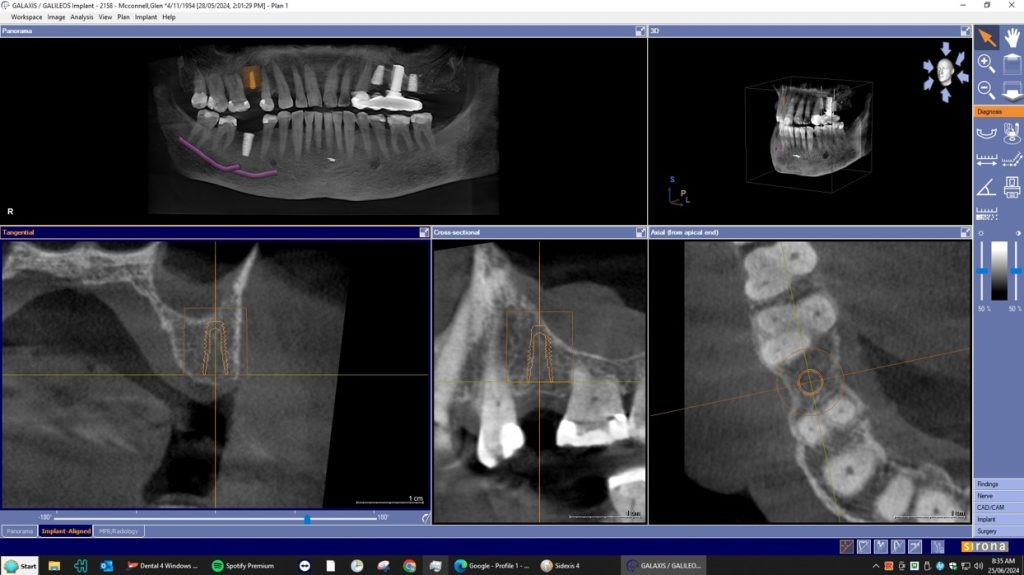

A dental Implant is a titanium “root” that integrates directly with the surrounding bone and replaces the function of the natural tooth. Neoss Implants are made using the best quality medical grade titanium, which is well known for its proven biocompatibility, and have a treated surface to facilitate bone integration.

The aim is to improve your health, chewing function and/or aesthetic appearance and once healing and restoration is complete you will be able to enjoy a wide variety of foods again.